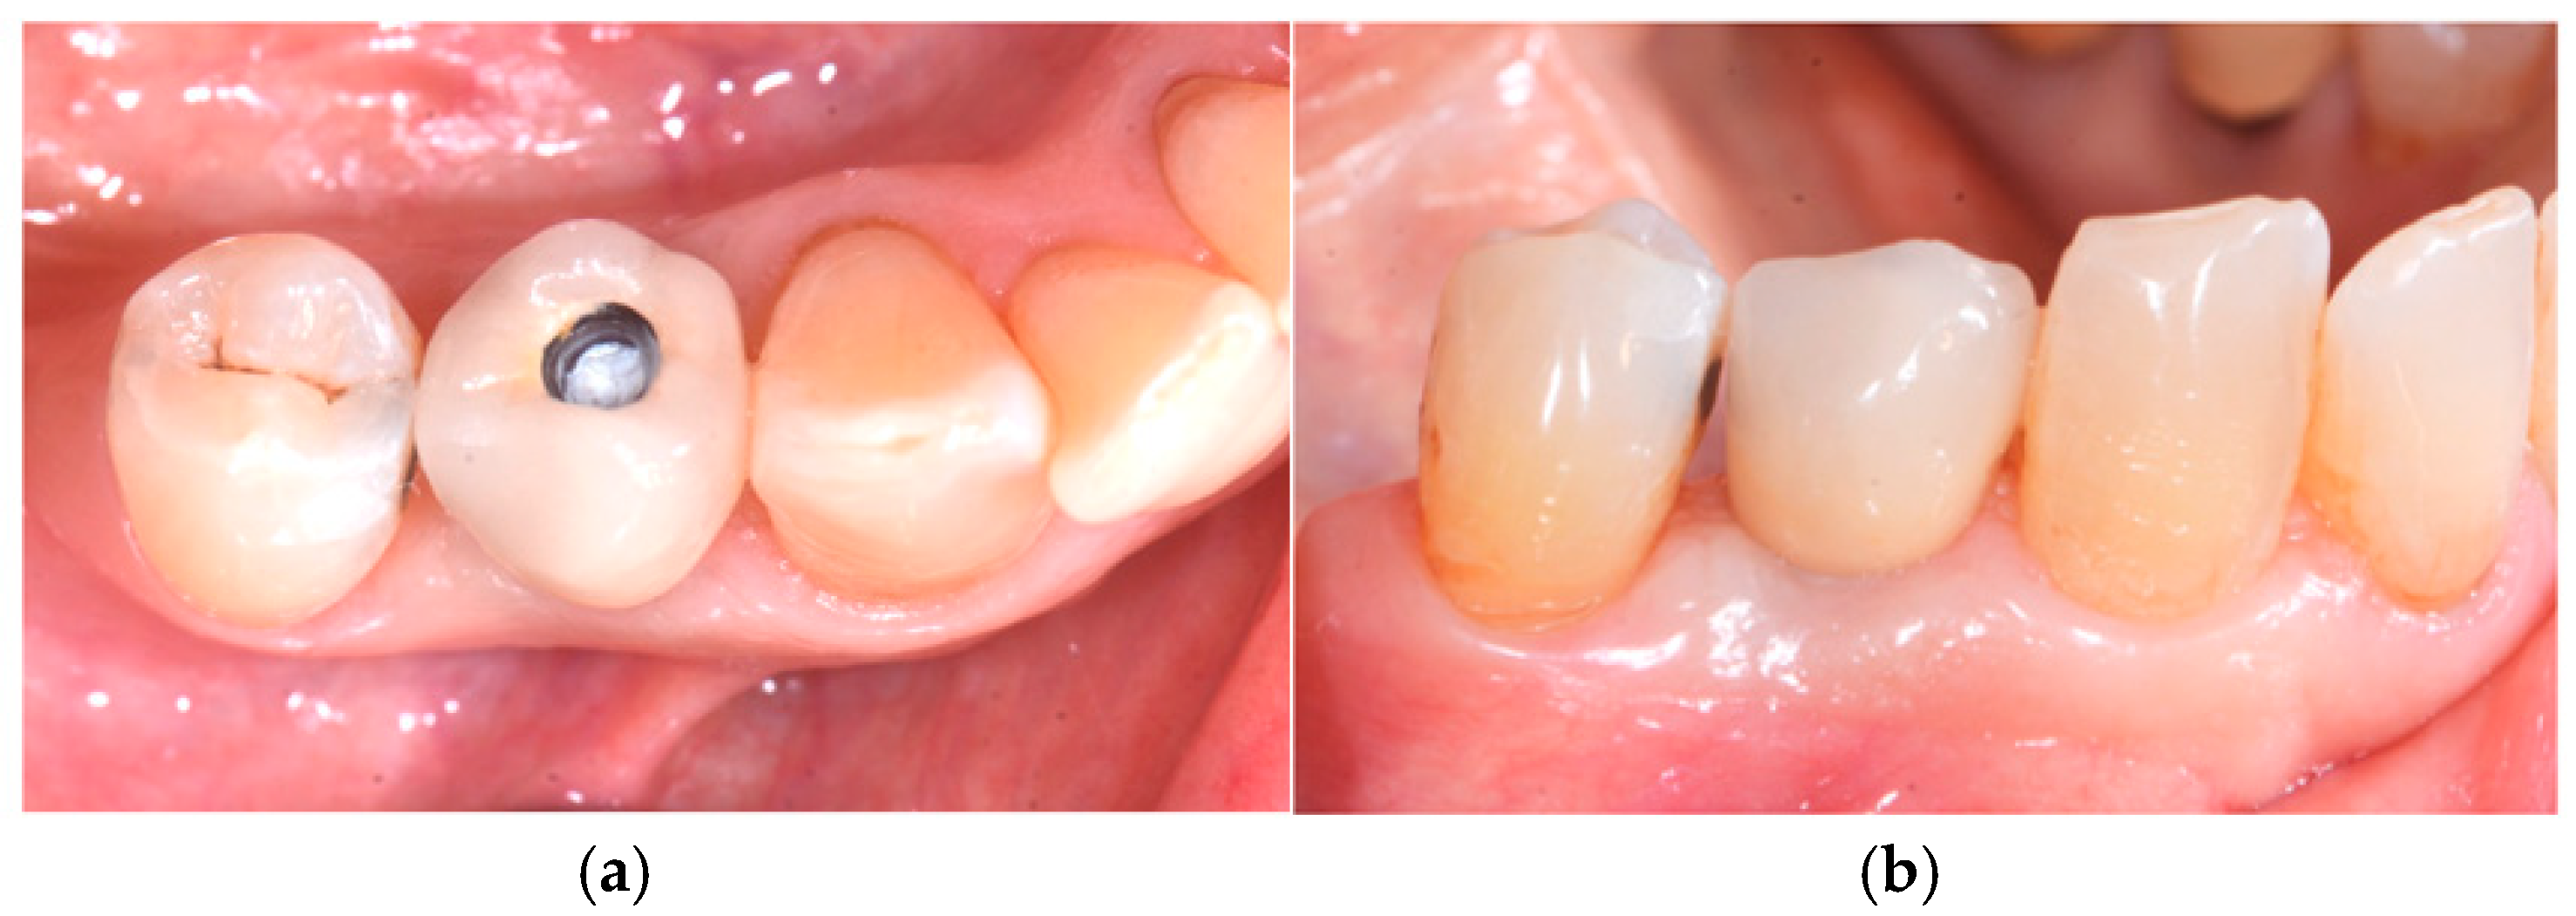

One month after surgery, a soft-tissue check was performed, which confirmed excellent soft-tissue healing with no loss of volume (Figure 3a,b).

Figure 3. Tissue healing after 1 month: (a) occlusal view and (b) buccal view.